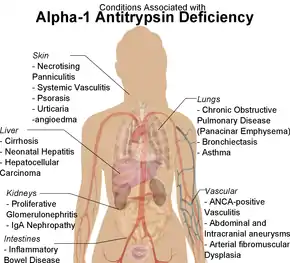

Alpha-1 antitrypsin deficiency (A1AD or AATD) is a genetic disorder that may result in lung disease or liver disease.[1] Onset of lung problems is typically between 20 and 50 years of age.[1] This may result in shortness of breath, wheezing, or an increased risk of lung infections.[1][2] Complications may include chronic obstructive pulmonary disease (COPD), cirrhosis, neonatal jaundice, or panniculitis.[1]

Individuals with A1AD may develop emphysema,[1] or chronic obstructive pulmonary disease during their thirties or forties even without a history of smoking, though smoking greatly increases the risk.[7] Symptoms may include shortness of breath (on exertion and later at rest), wheezing, and sputum production. Symptoms may resemble recurrent respiratory infections or asthma.[8]

A1AD may cause several manifestations associated with liver disease, which include impaired liver function and cirrhosis. In newborns, alpha-1 antitrypsin deficiency can result in early onset jaundice followed by prolonged jaundice. Between 3% and 5% of children with ZZ mutations develop life-threatening liver disease, including liver failure.[9] A1AD is a leading reason for liver transplantation in newborns.[9] In newborns and children, A1AD may cause jaundice, poor feeding, poor weight gain, hepatomegaly and splenomegaly.[9]

Apart from COPD and chronic liver disease, α1-antitrypsin deficiency has been associated with necrotizing panniculitis (a skin condition) and with granulomatosis with polyangiitis in which inflammation of the blood vessels may affect a number of organs but predominantly the lungs and the kidneys.[10]